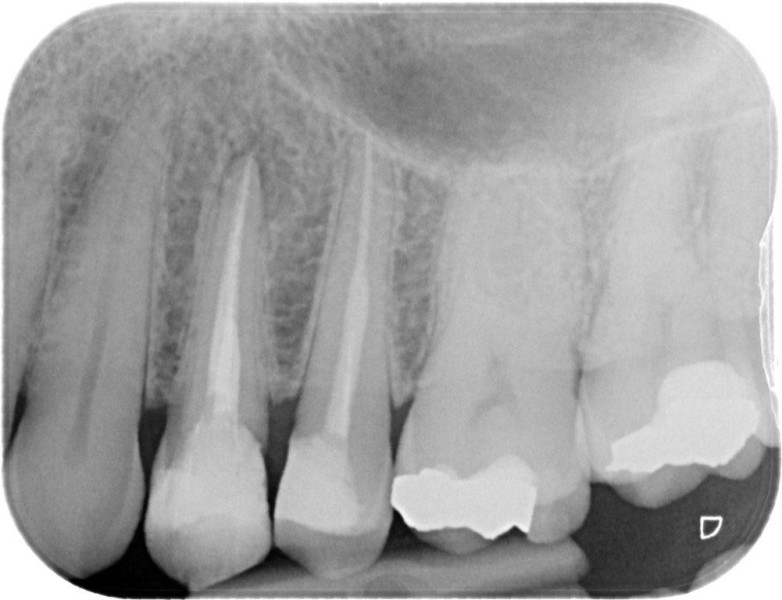

Premolar retreatment